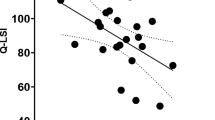

Brain activity in somatic sensation areas was lower in the MPFL deficiency group than in the control group. The areas that showed more activation in the task phase than in the rest phase are different between both groups on images of the brain map (Fig. 1). Results of comparisons between groups showed MRI signal changes in the contralateral primary sensory area (% signal change for MPFL group, 0.49%, versus 1.1% for the control group; p < 0.001), thalamus (0.2% versus 0.41% for the MPFL versus control, respectively; p < 0.001), ipsilateral thalamus (0.02% versus 0.27% for the MPFL versus control, respectively; p < 0.001, and cerebellum (0.82% versus 1.25% for the MPFL versus control, respectively; p < 0.001) were lower in the MPFL deficiency group than in the control group (Table 2). The mean values and SD of percent signal change in these areas are shown (Fig. 2). To the contrary, brain activity was higher in the contralateral primary motor area (1.06% versus 0.6% for the MPFL versus control, respectively; p < 0.001), supplementary motor area (0.89% versus 0.52% for the MPFL versus control, respectively; p < 0.001) and visual cortex (0.86% versus 0.14% for the MPFL versus control, respectively; p < 0.001) in the MPFL deficiency group than in the control group (Fig. 3).

The percent signal change in the area was activated higher in the control than in the medial patellofemoral ligament (MPFL) deficient group (p < 0.001). The mean value and SD are shown. M1 = primary motor area; SMA = supplementary motor area; PF = prefrontal lobe; IP = inferior parietal lobe; ACC = anterior cingulate cortex; V= visual cortex; ips = ipsilateral.

Additionally, the areas related to emotion were activated in the MPFL deficiency group. Intergroup analysis showed higher MRI signal changes than those in the control group in the contralateral inferior parietal lobule (0.89% versus 0.62% for the MPFL versus control, respectively; p < 0.001), prefrontal lobe (1.09% versus 1.09% for the MPFL versus control, respectively; p < 0.001), anterior cingulate cortex (0.84% versus 0.08% for the MPFL versus control, respectively; p < 0.001), vermis (1.18% versus 0.37% for the MPFL versus control, respectively; p < 0.001), and ipsilateral prefrontal lobe (Table 2). The mean value and SD of MRI signal changes are shown (Fig. 3).